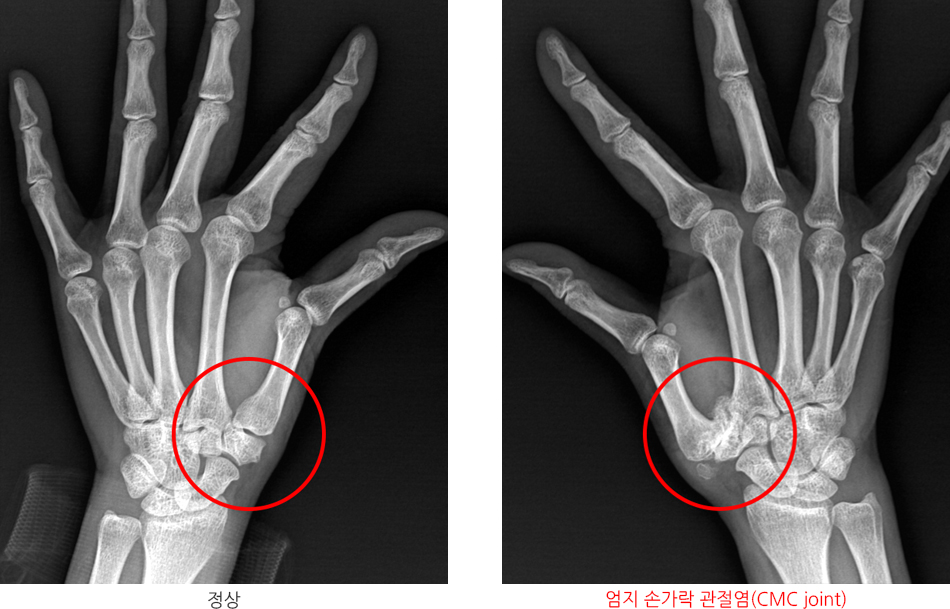

손가락 관절염은 관절에 염증이 발생하여 통증과 불편함을 유발하는 질환입니다. 이 질환은 크게 골관절염과 류마티스 관절염으로 나눌 수 있습니다. 골관절염은 나이와 관련된 퇴행성 질환이며, 류마티스 관절염은 면역 체계의 이상으로 발생합니다. 각각의 원인을 자세히 살펴보겠습니다.

골관절염은 손가락 관절에 가장 흔하게 발생하는 유형입니다. 이는 주로 나이와 관련이 있습니다. 나이가 들수록 연골이 약해지고 마모되어 통증과 이동성 감소를 유발합니다. 이 외에도 다음과 같은 요소들이 골관절염과 관련될 수 있습니다: